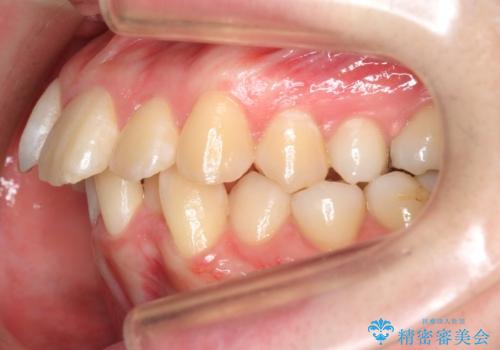

20代女性 前から5番目の歯を抜歯

- 前歯のがたつき、前突を主訴に来院。

通常前から4番目の歯を抜歯するのですが、左上5番の形が矮小であったため、そちらを抜歯しました。(患者様の希望にそっています。)

前から5番目の歯を抜くと、長くて1年ほど矯正期間が延長しますが、形に異常がない左上4番を抜かずに保存しています。

治療は長くかかりましたが、正常な形の歯をのこすことができました。